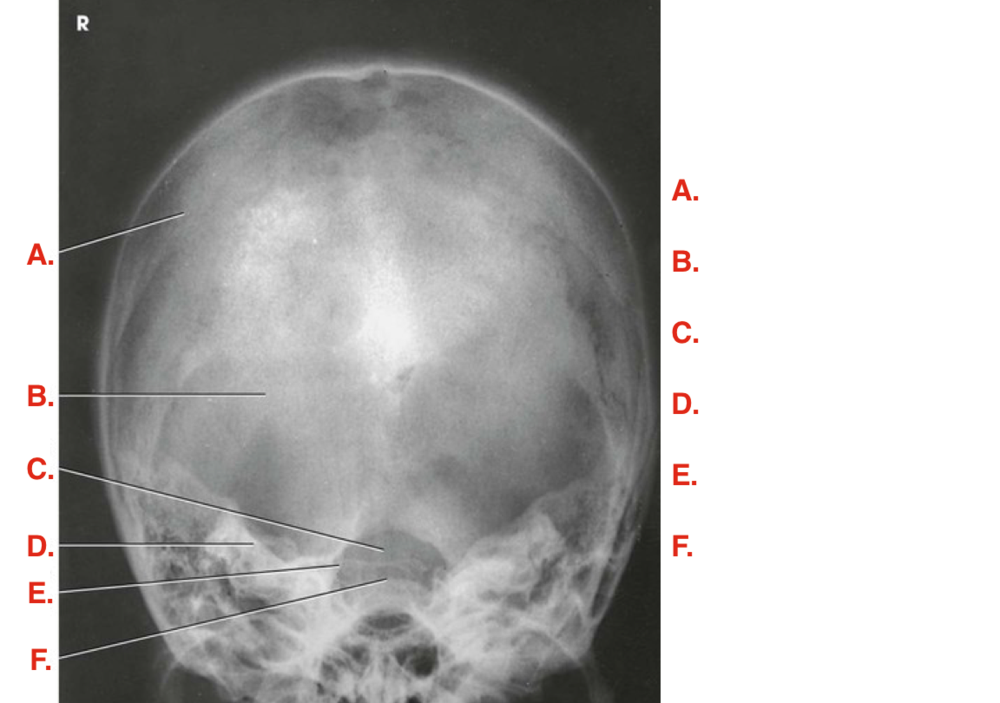

Question 4

Question

Label the image

Image:

fda4183e-033f-4d44-8d15-2496855e8ac0 (image/png)

Answer

frontal sinus

crista galli

superior orbital margin

superior orbital fissure

ethmoidal sinus

petrous ridge

inferior orbital margin

inferior orbital fissure